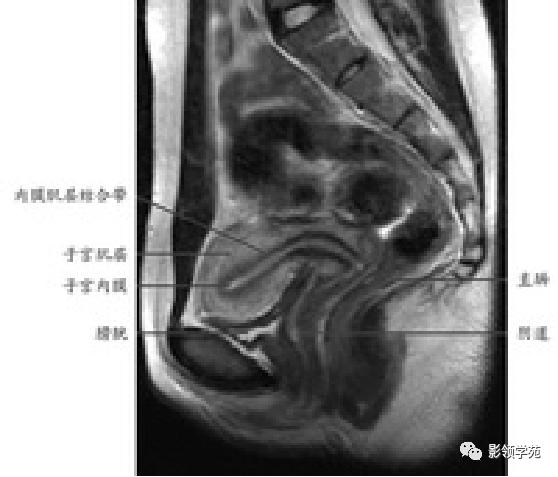

T2WI : 宫体三层:

中心高信号---子宫内膜和分泌物;

中间低信号带---子宫肌内层,亦称结合带;

周围呈中等信号---子宫肌外层

子宫

T2WI图像可显示子宫体三层

结构

- 子宫内膜-高信号

- 结合带-低信号

- 子宫肌层-中等信号

子宫体正常MRI表现